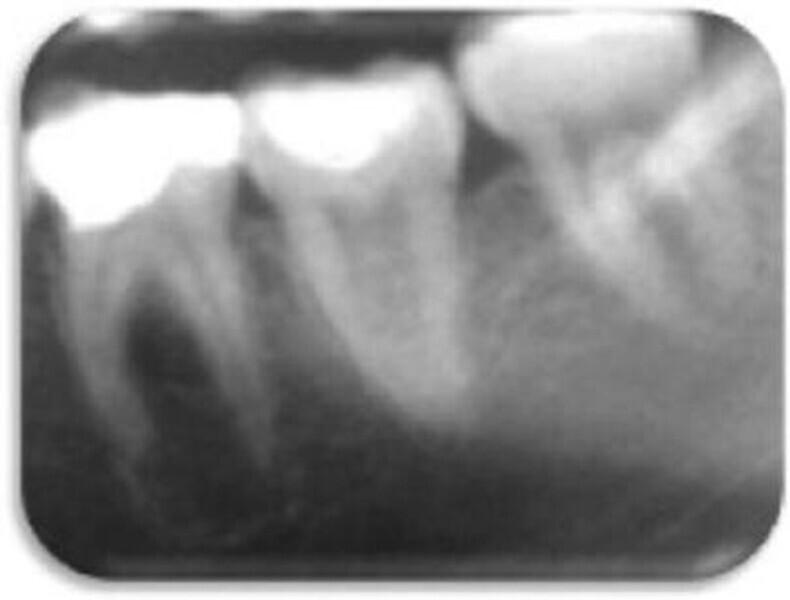

Leczenie endodontyczne autogennego przeszczepu zęba